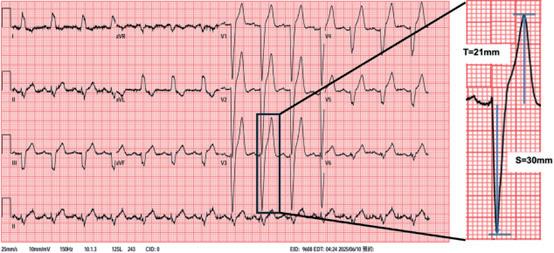

一名 69 歲男性,有高血壓及高血脂病史,因胸悶合併心悸至本院急診就診,心電圖顯示新發生的左束支傳 導阻斷 (left bundle branch block, LBBB) ( 圖一 ) 。病人曾接受多切心臟電腦斷層掃描顯示無明顯冠狀動脈狹窄, 且心臟超音波顯示左心室收縮功能正常且無心室肥厚,排除急性冠心症後返回門診追蹤。病人自述胸悶且心搏 過速時,智慧型手錶會顯示寬的 QRS 波心電圖,當回復窄的 QRS 波時症狀即緩解,臨床診斷懷疑是 painful LBBB症候群。初期以乙型阻斷劑控制症狀,但日常活動時仍間歇發作,後續嘗試以茶鹼(theophylline 100mg BID) 治療後,目前症狀緩解未再復發,後續心電圖並未有 LBBB 之情形 ( 圖二 ) ,且智慧型手錶顯示寬的 QRS 波心電圖 頻率也大幅下降。

LBBB 可見於多種心臟病理或隨年齡增加而出現,但大多不伴隨典型胸痛,而 painful LBBB 症候群定義為 每當 LBBB 發生就伴隨胸痛,通常與速率相關,且須排除心臟缺血。機轉推測為心室不同步收縮導致心肌張力 與牽張改變,而引起胸痛症狀。與慢性 LBBB 有所區別,文獻中提及 painful LBBB 症候群的心電圖胸前導程會呈 現極低的 S/T wave ratio(<1.8) 及 inferior QRS axis ,本個案有低的 S/T wave ratio 為 1.43 。此症候群多為速率相關 ( 如運動、情緒或心率上升時出現 ) ,常導致病人被延誤診斷,或反覆至急診就診或接受檢查。文獻建議首選為心 率控制 ( 乙型阻斷劑或 ivabradine) ,另可藉運動訓練提高出現 LBBB 的心率閾值,亦有茶鹼 (theophylline) 治療成 功之個案報告。當藥物治療失敗時,有報導指出傳導系統刺激 (Conduction System Pacing) 如 His bundle pacing 與 left bundle branch area pacing 可恢復生理性心室去極化來緩解症狀。本個案因無適應症裝置心臟節律器,經向 病人說明後使用茶鹼控制症狀,目前於心臟內科門診穩定追蹤中。

(圖一)、 急診時12導程心電圖顯示左束支傳導阻斷, 其V3 S/T ratio為1.43 (<1.8) (圖二)、 後續於門診接受茶鹼 (theophylline) 治 療後LBBB未再復發